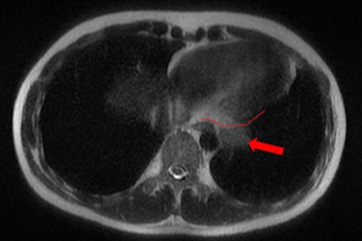

A 28-year-old male patient presented with onset of pain on his left hemithorax and progressive fatigue, in September, 2020. He had no previous comorbidities. An investigative MRI (magnetic resonance imaging) scan showed a large and heterogeneous mass on his left hemithorax with partial lung atelectasis, inferior displacement of diaphragm, mediastinal shift to the right and small pleural effusion (Figures 1a, 1b and 1c). The tumor was in contact with the inferior esophagus and the descending aorta. The thoracic wall (muscle and ribs) was not compromised. These findings suggested, possibly, a mass of pleural origin. An initial core-needle biopsy was performed in October, 2020 to clarify the diagnosis.

Figure 1a: Large solid mass (24 x 10.5 x 14.5 cm) with hemorrhagic areas and heterogeneous post contrast enhancement on the left pleural space.

Figure 1b: The lesion pushes downward the diaphragm, promotes lung atelectasis and displaces mediastinal structures to the right. Minimum pleural effusion is associated (x).

Figure 1c: The mass also and extends to the posterior mediastinal fat (line) close to the descending aorta (star) and esophagus (empty arrow).